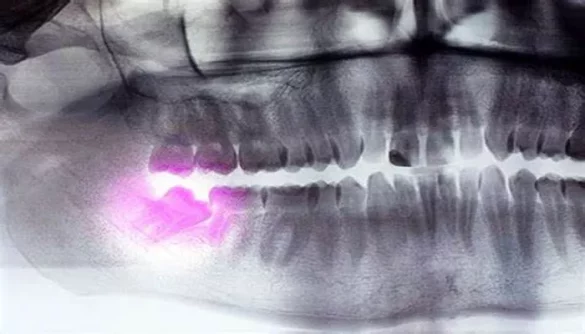

10. Cyst Formation Around the Tooth

In some cases, cysts can develop around the wisdom teeth as they erupt. These cysts are usually fluid-filled sacs that can cause pain, swelling, and damage to surrounding tissues, including the jawbone and teeth.

What Are the Signs of a Cyst?

Increased swelling or tenderness around the wisdom tooth

Pain that persists or worsens

A noticeable lump or bump in the gums

What Should You Do?

If you suspect the formation of a cyst, seek immediate dental care. Your dentist may recommend removing the cyst and the affected wisdom tooth to prevent further complications.